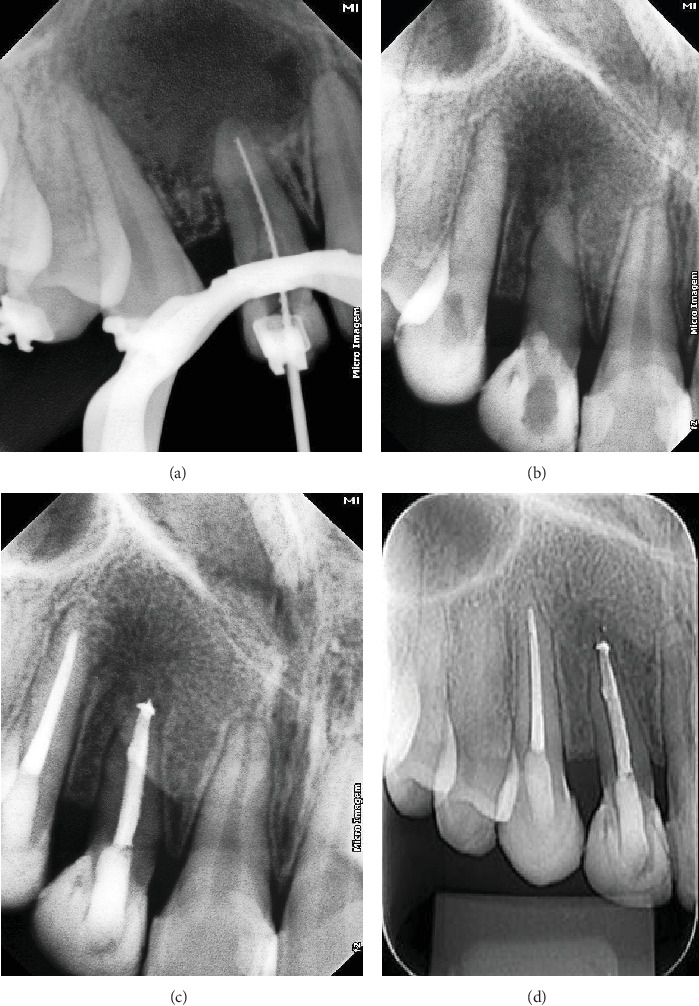

Dens invaginatus (DI) is a developmental anomaly that affects teeth. This case report demonstrates the successful endoaesthetic management of a Type II DI in the maxillary right lateral incisor (Tooth 12). A 12-year-old female patient presented with pain and swelling in Tooth 12, which had previously been diagnosed with DI and accessed endodontically. The patient was also concerned about the aesthetic appearance of her anterior teeth. Clinical, radiographic, and tomographic findings confirmed Oehler's type II DI, with root perforation and an apical abscess in Tooth 12, as well as pulp necrosis in Tooth 13. Nonsurgical root canal treatment was recommended for both teeth, with additional root perforation repair for Tooth 12. Multiple visits were required for nonsurgical endodontic therapy. During the initial visit, the perforation was identified and sealed, followed by chemomechanical preparation and placement of calcium hydroxide paste. Ten months later, the root canals were filled. After endodontic treatment, the patient underwent in-office bleaching, followed by composite resin veneers on the upper anterior teeth, using the preformed metal matrix technique. This resulted in excellent aesthetic outcomes. At the 2-year follow-up examination, the patient remained asymptomatic, and radiographic assessment showed complete resolution of the periapical lesion. This case highlights the importance of multidisciplinary collaboration, precise treatment planning, and patient-centered care in achieving optimal endoaesthetic results in complex cases.